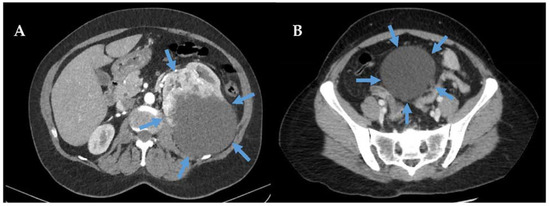

- Yim, H.; Tang, Y.L.; Tandon, A.A. Multifocal Retroperitoneal and Pelvic PEComas Mimicking Liposarcoma: A Case Report and Review of Literature. Radiol. Case Rep. 2021, 16, 2624–2629. [Google Scholar] [CrossRef]